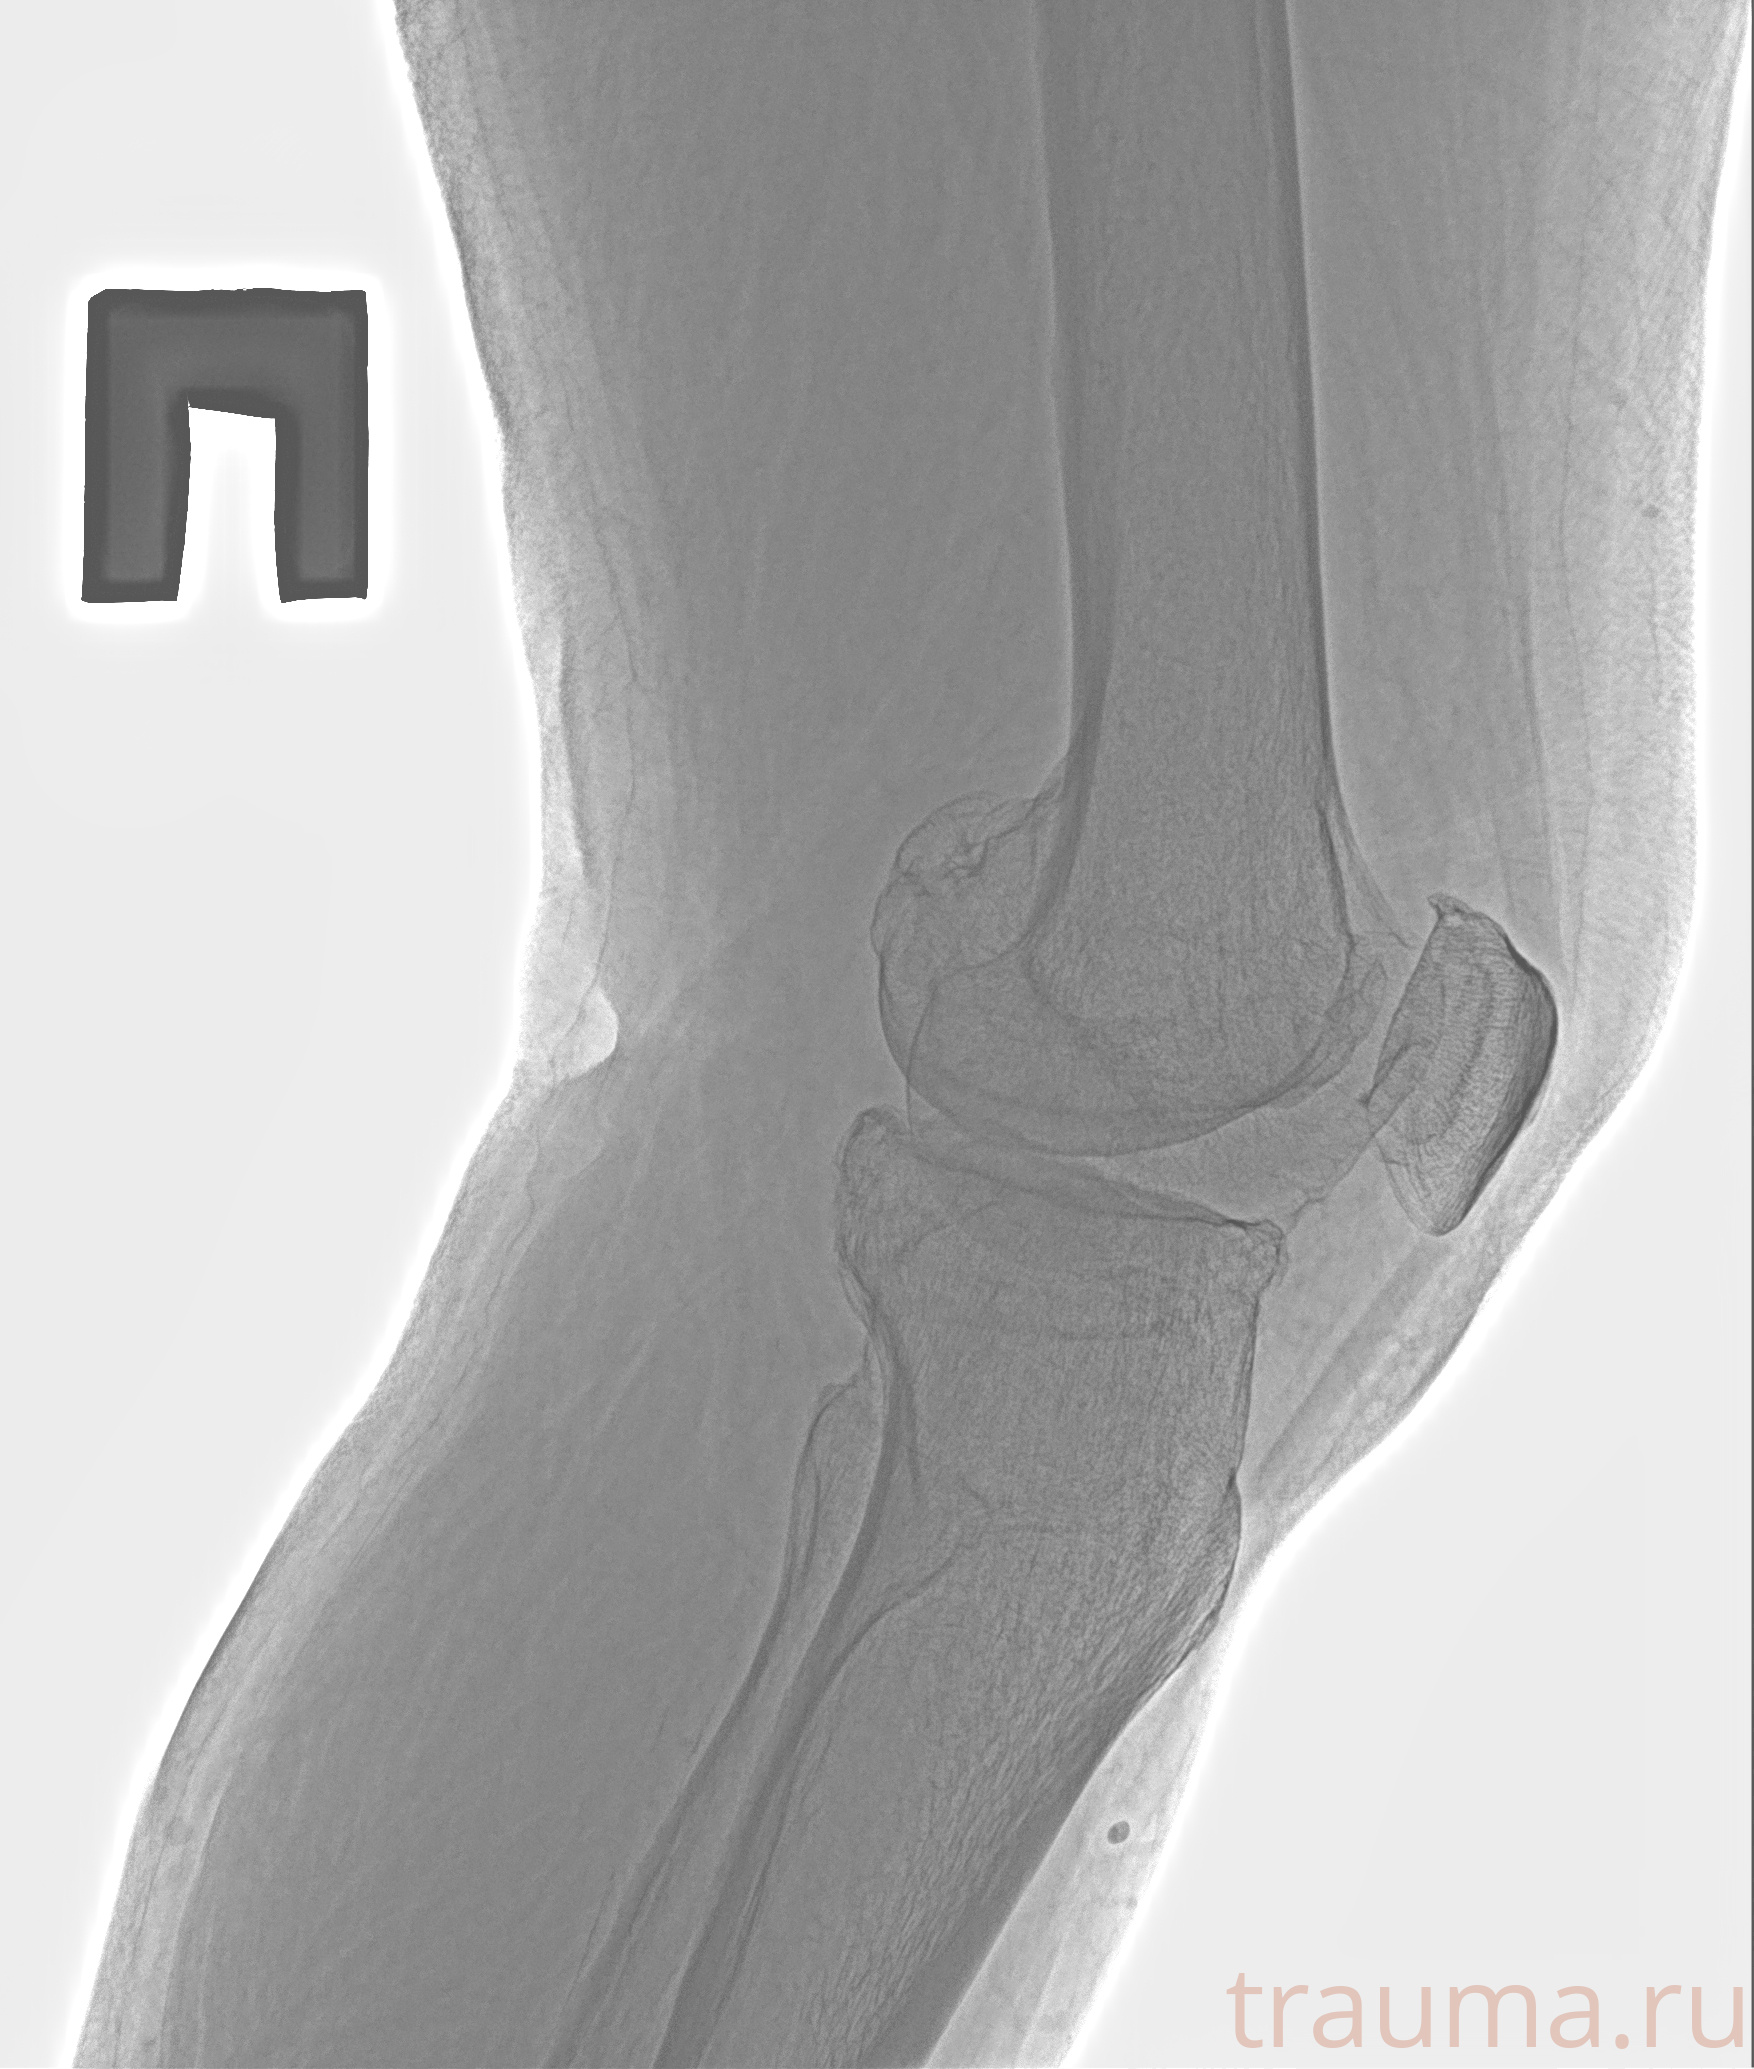

Рентгенограммы

Рентген на дому: по вашему адресу приезжает врач-рентгенолог, травматолог-ортопед с мобильным рентгеновским аппаратом, проводит диагностику травмы или заболевания, делает необходимые рентгенограммы, дает рекомендации по дальнейшему лечению. Получить качественные снимки в домашних условиях возможно благодаря уникальной методике, разработанной МосРентген Центром для института  Склифосовского